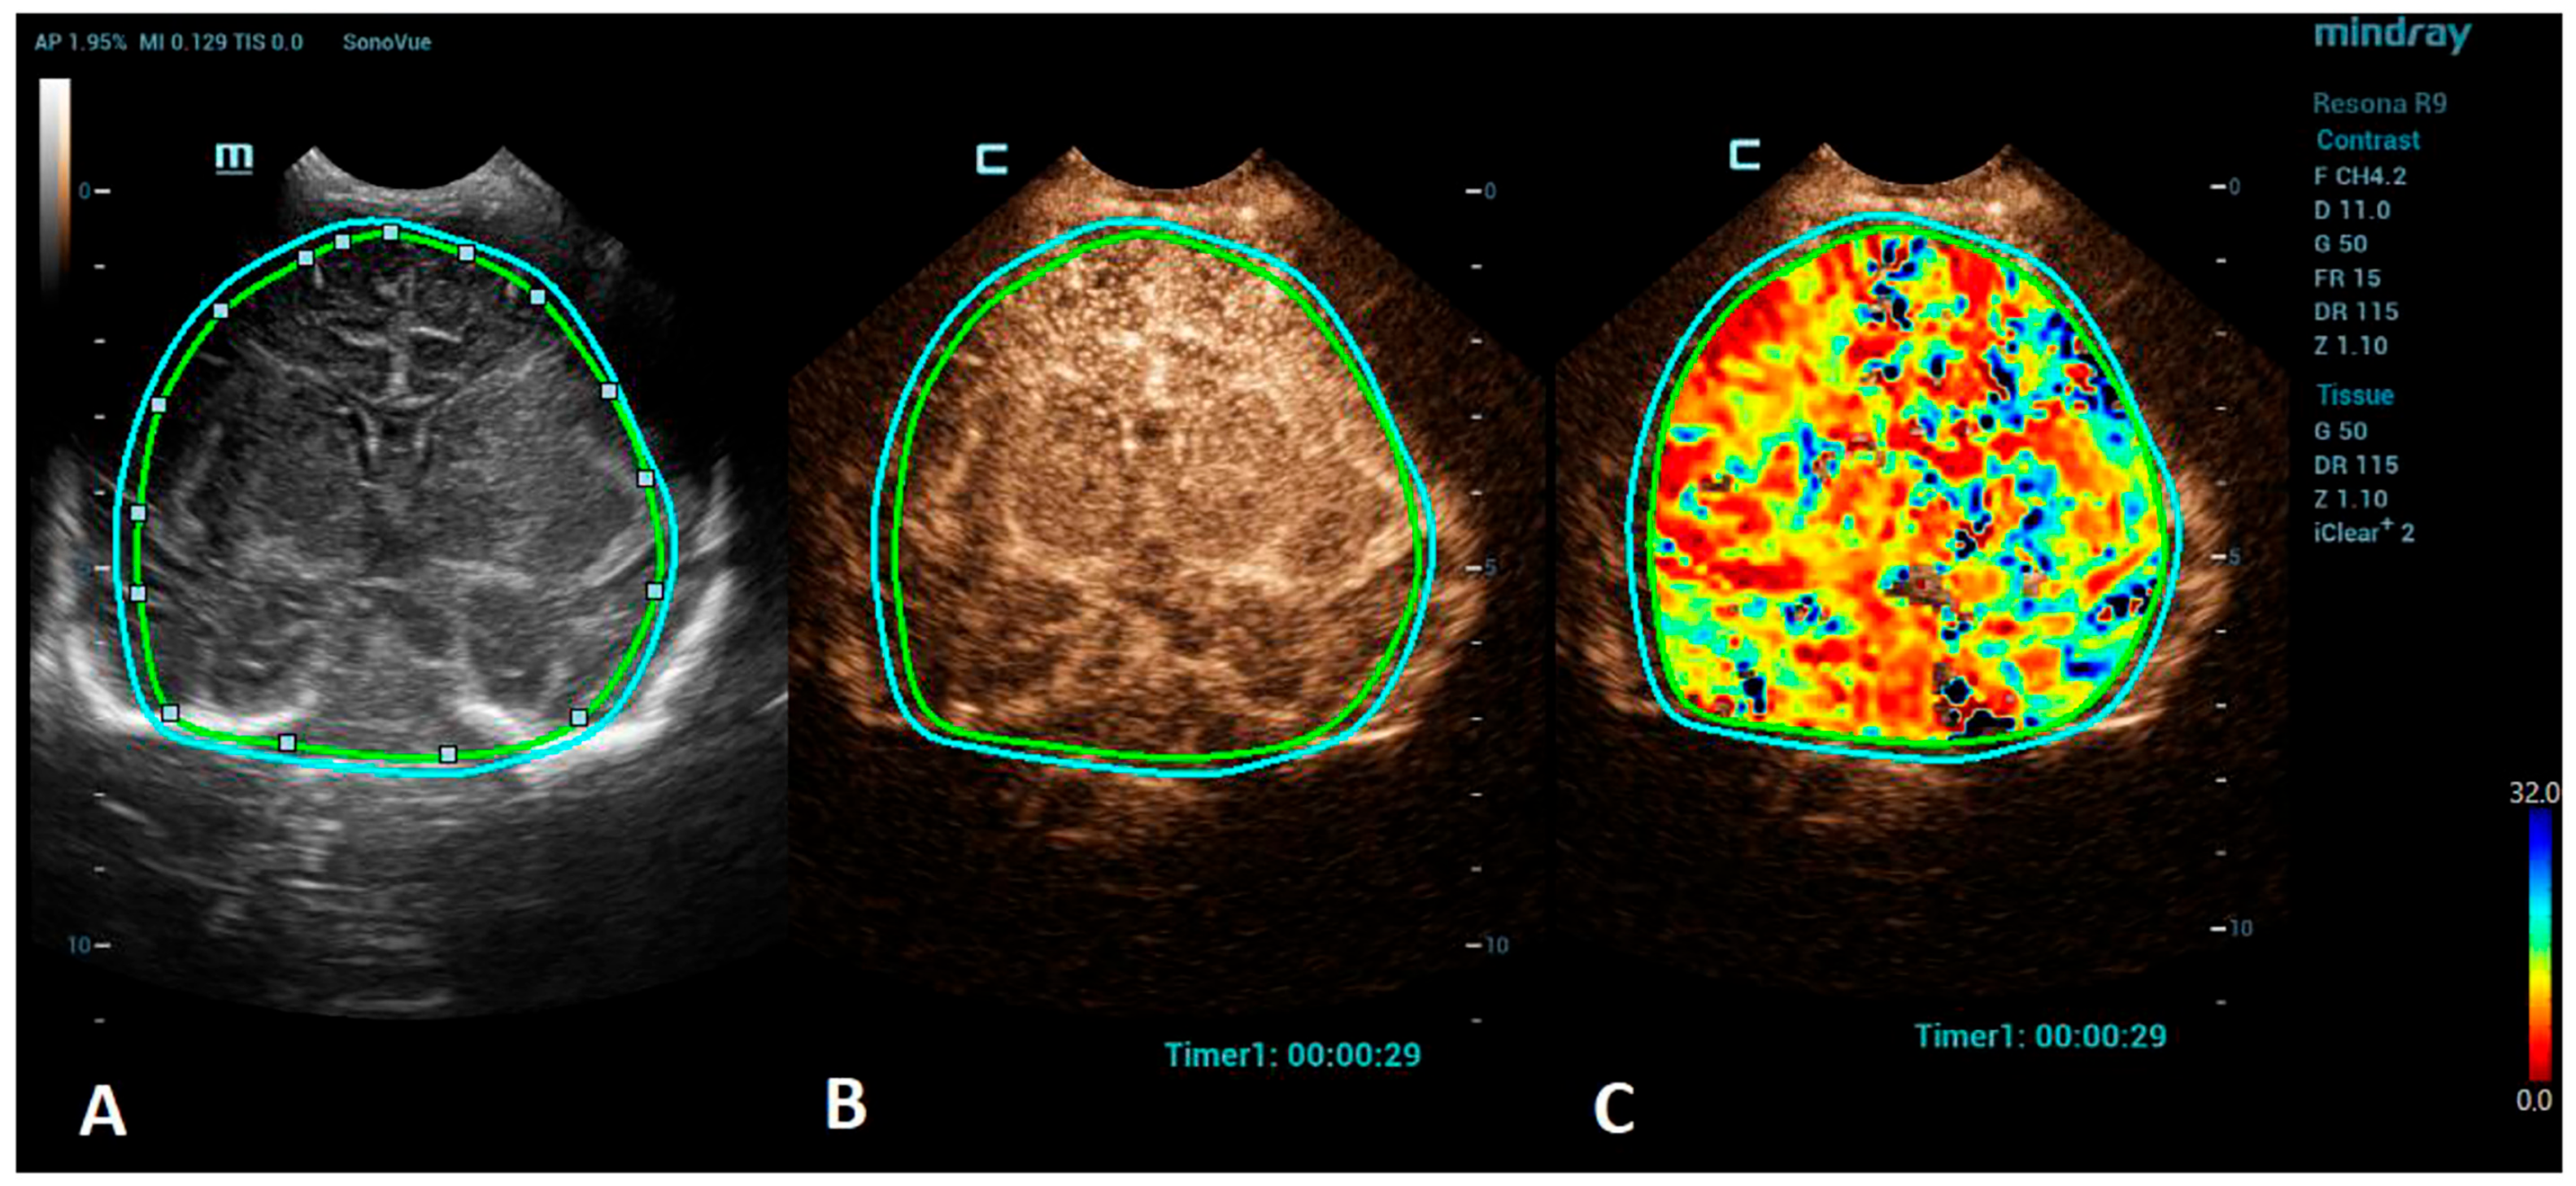

Figure 2.

A VueBox® analysis of a 5-day-old male with ischemic stroke in the territory of the left middle cerebral artery. (A) The coronal grayscale reference ultrasound image of the brain. (B) The coronal CEUS image. (C) The coronal CEUS perfusion map highlighting an increased fall time parameter in the territory of the left middle cerebral artery. The whole brain is selected as a region of interest in the presented image (marked by the two color lines).

Advances in clinical recognition and radiological imaging methods have increased the ability to diagnose ischemic stroke among children. Imaging studies can help distinguish ischemic infarction from cerebral hemorrhage and other causes of sudden neurologic symptoms [44]. MRI has become the first-line neuroimaging modality to confirm the clinical diagnosis of ischemic stroke and should always be preferred to CT due to its greater specificity and sensitivity [40]. MRI, including diffusion-weighted imaging (DWI) and apparent diffusion coefficient (ADC) maps, can demonstrate evidence of an infarction even in the first few hours after the onset of symptoms [45]. Perfusion imaging, such as arterial spin labeling (ASL) sequence, allows the measurement of cerebral blood flow and volume and can detect areas of ischemia without the use of a contrast agent [46]. Cerebral angiography is still considered the best method to visualize the intracranial vasculature; however, continued refinements in MR angiography (MRA), especially time-of-flight angiography (TOF), which allows the visualization of flow within vessels without contrast administration, have made MRA a feasible noninvasive alternative for children, sparing the child from the potential harmful effects of ionizing radiation [47,48]. However, in critically ill neonates, the utilization of MRI can be limited due to the risks associated with transportation and incompatible support equipment. CEUSs, with their potential to evaluate brain microvasculature, present a great emerging imaging alternative. CEUSs have been used for the evaluation of acute ischemic stroke among an adult population to detect cerebral perfusion deficits and to monitor the responses to a thrombolytic treatment [49,50]. The number of studies on a pediatric population, so far, are minimal, but CEUSs have been shown to have good sensitivity to detect acute ischemic stroke in comparison to MRI [51]. For the imaging of stroke using CEUS, the quantitative brain perfusion analysis is typically performed. CEUS shows a delayed rate of the washout of the contrast agent and a delayed time-to-peak in the affected areas [49] (Figure 2). Future research via larger prospective studies is needed to better determine the diagnostic accuracy of CEUSs in comparison to MRI for the detection of stroke and its utility for the accurate characterization of the penumbra for monitoring the responses to thrombolytic therapy.